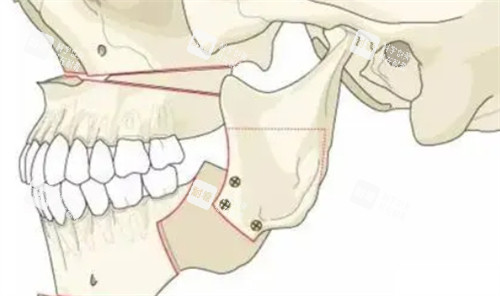

2. 上颌Le Fort I型截骨术

1. 切口:上颌前庭沟切口。

2. 剥离:显露上颌骨前壁和外侧壁。

3. 截骨:按预定设计截断上颌骨。

4. 移动:将上颌骨段移动到设计位置。

5. 固定:使用钛板进行坚强内固定。

6. 缝合:关闭切口。

3. 下颌升支矢状劈开截骨术

1. 切口:下颌升支前缘切口。

2. 剥离:显露下颌支内侧。

3. 截骨:完成矢状骨切开。

4. 劈裂:分离近远心骨段。

5. 移动:按设计调整下颌位置。

6. 固定:确认髁突复位后固定。

7. 缝合:关闭切口。